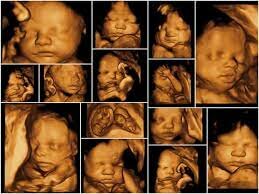

• 3D Ultrasound Tech.

3D Ultrasound Tech.

Kazunori Baba of the University of Tokyo developed 3D ultrasound technology and captured three-dimensional images of a fetus in 1986.

• 4D Tech.

4D Tech.

the adoption of 4D (real time) capabilities. Ultrasound guided biopsies (endoscopic ultrasounds) also began in the 1990s. Similar to a 3D ultrasound, except it displays the images of the baby in a live-streaming video.